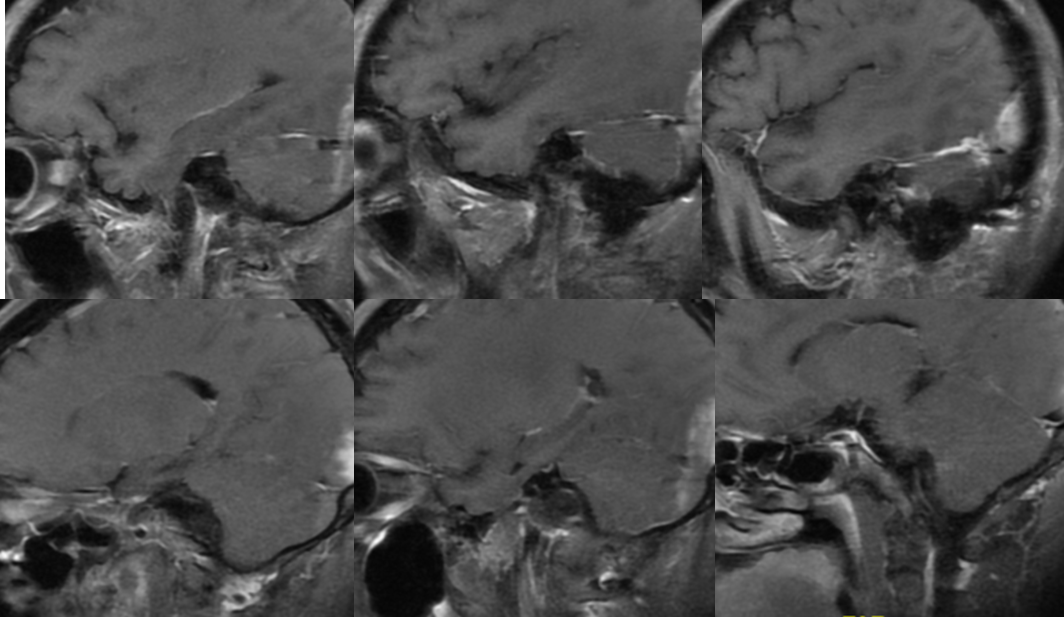

术前影像

![]()